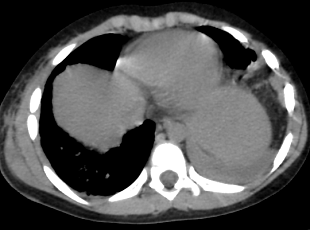

В хирургическое отделение ПК СОКБ после ДТП поступил ребенок с крайне редкой торако-абдоминальной травмой - двухсторонним разрывом диафрагмы с перемещением органов брюшной полости в грудную клетку. Торакотомическим и лапаротомическим доступом произведена пластика диафрагмы с 2х сторон после низведения органов брюшной полости.